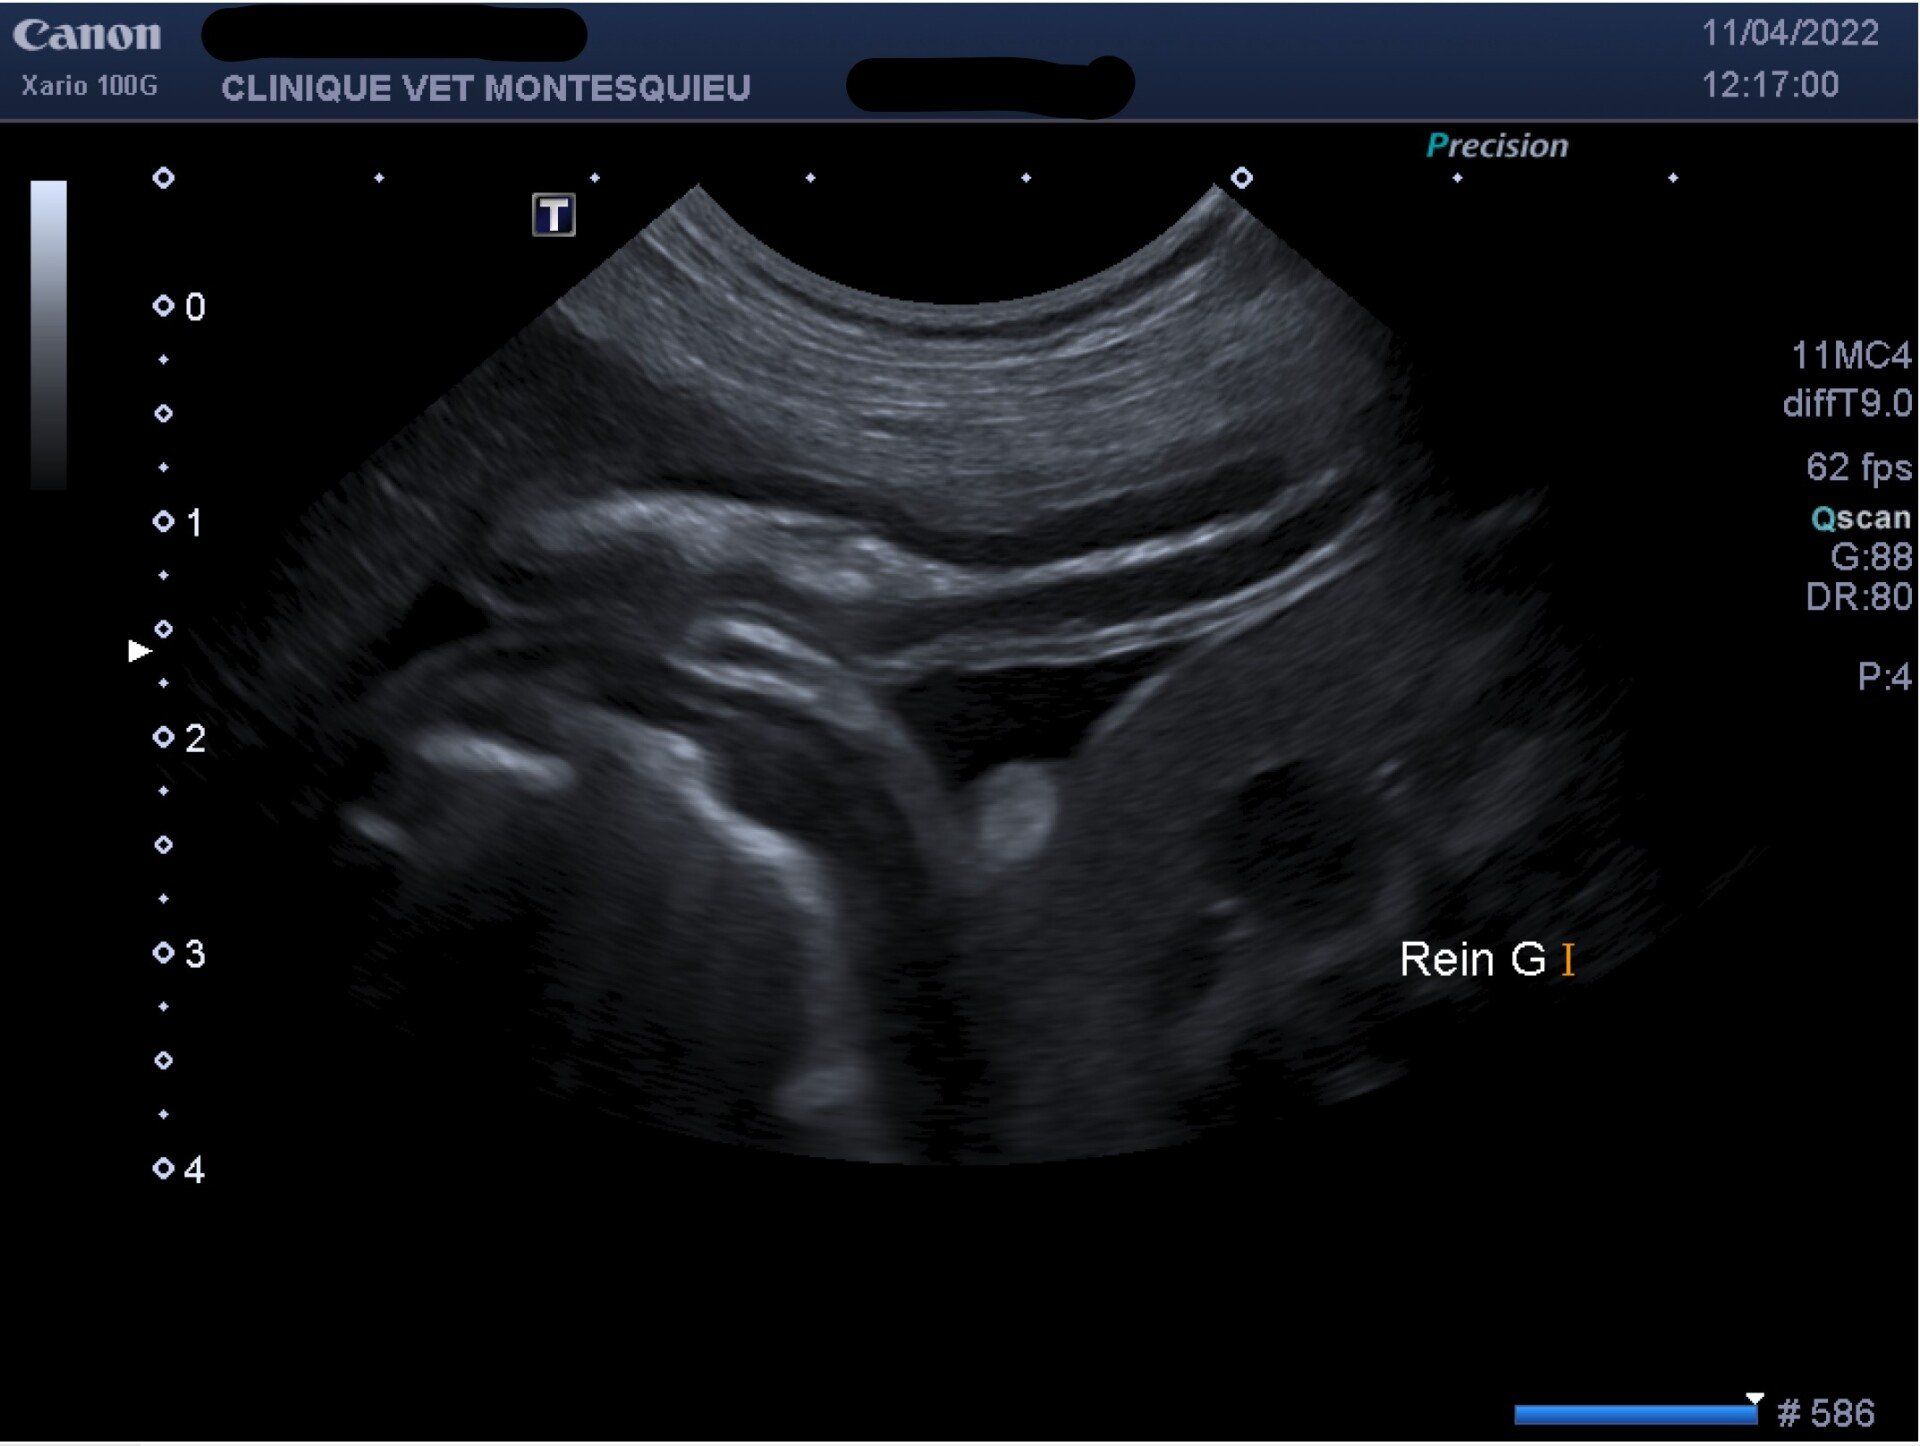

- Echographie abdominale

L'échographie abdominale est pratiquée quotidiennement au sein de nos établissements. Cette technique d'exploration permet de diagnostiquer des maladies mais également d'en suivre l'évolution à travers l'observation de la forme et de la structure des organes. Forme, dimensions, structure, aspect des différents tissus sont autant d'éléments qui vont renseigner le praticien.

Les vétérinaires vont ainsi pouvoir évaluer différents organes tels que : le foie, les reins, les glandes surrénales, les ganglions lymphatiques, l'estomac et les différents composantes du tubes digestifs, le pancréas, la rate, la vessie et le système urinaire, la prostate, le système reproducteur...

Les échographies approfondies font l'objet d'un compte-rendu synthétisant les observations du vétérinaire et des principales mesures accompagnées des images les plus pertinentes.